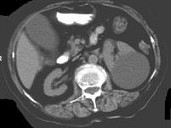

- 多项选择题女,38岁, 左腰部胀痛不适,CT平扫+增强如图所示, 下列说法正确的是 ( )

A、平扫时可见左肾一类圆形囊性病灶

B、病灶边界清晰,表面光整

C、增强扫描皮质期和实质期该病灶均未见强化

D、考虑为左肾囊性肾癌

E、考虑为左肾囊肿